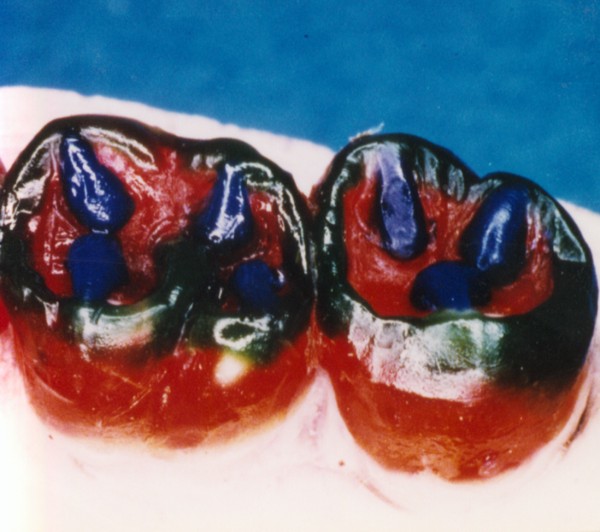

Primera Parte RESUMEN: La alta complejidad inherente a los procedimientos de Rehabilitación Oral, obligan al profesional que la ejerce a basarse en parámetros multidisciplinarios, a veces lo suficientemente intrincados que hacen imposible la práctica de la misma, sin la presencia en su mente de una clara concepción de la Oclusión. The extreme complexity of Oral Procedures, make it imperative for the working professional to rest on multidisciplinary parameters, sometimes so complex that make impossible its practice without the presence of a clear idea of Oclusion. DESARROLLO Suele ser sumamente árido el abordaje de un tema como Oclusión, desde la perspectiva de nuestro diario trabajo ,con todo el strees que este conlleva, con toda la lucha que significan citas, honorarios, diferentes personalidades de los pacientes, inquietudes de los mismos, etc. «LA MEJOR OCLUSIÓN ES LA QUE TIENE LA MEJOR DESOCLUSIÓN» Básicamente, podemos como desde hace ya muchos años se viene haciendo; clasificarlos en: A)Determinantes Posteriores (fijos) Más contemporáneamente, en: I-Mecanismos Primarios: A.T.M. GUIA ANTERIOR INCLINACIÓN DEL PLANO OCLUSAL CURVA SAGITAL DE SPEE FORMA DE LA ARCADA III-Mecanismos Elementales CRESTAS TRIANGULARES INTERNAS Analicemos cada uno de ellos: Es evidente, que la reproducción de las características de la A.T.M., en nuestro aliado fundamental, el Articulador; es imprescindible. Partiendo de la premisa de obtener una OCLUSIÓN MUTUAMENTE PROTEGIDA, para luego arribar al concepto de OCLUSIÓN MUTUAMENTE COMPARTIDA, concepto este que desarrollaremos durante el transcurso de las distintas entregas, analizaremos cada uno de los FACTORES DETERMINANTES DE LA OCLUSIÓN. El primero de ellos, por ser fijo e invariable, solo diremos que: son sus INCLINACIONES PLANARES, o sea : A-INCLINACIÓN DE LA TRAYECTORIA CONDILEA C-BENNET INMEDIATO articuladores totalmente ajustables) D-DISTANCIA INTERCONDILAR. En cuanto a la GUÍA ANTERIOR, mecanismo primario y por supuesto anterior, provee al cuerpo mandibular; del camino a recorrer durante las excursiones protrusivas y lateralidades, a través del vínculo entre las piezas dentarias anteriores, superiores e inferiores. En un corte sagital, podemos observar la relación entre estos donde vemos que se vinculan sin entrar en un contacto franco, sino más bien en una relación de vencindad muy intima a la que llamamos: PUNTO DE ACOPLAMIENTO. Otros factores fundamentales de la GUÍA ANTERIOR son : A-ALTURA FUNCIONAL B-PUNTO DE ACOPLAMIENTO En cuanto a los SURCOS, sabemos que durante una Transtrusión, las cúspides fundamentales generan surcos sobre las piezas que antagonizan. Dichos surcos proveen de una vía de escape a las cúspides antagonistas para evitar colisiones, con las indeseables fuerzas laterales cuya gravedad ya conocemos. MECANISMOS SECUNDARIOS La CURVA FRONTAL DE WILSON, se observa invertida a nivel de los caninos y de los primeros premolares. El PLANO OCLUSAL, en realidad no es ningún plano, sino la sumatoria de muchos MICROPLANOS, los cuales individualmente pueden constituir factores presentes en la OCLUSIÓN, pero auténticos problemas para la DISCLUSIÓN. La CURVA SAGITAL DE SPEE, denominada originariamente de BALKWIL-SPEE, fue concebida como una curva. El cuarto factor SECUNDARIO: el ANCHO DE LA ARCADA, es evidente que variando los ejes de rotación , alrededor de las diferentes distancias ;cambiará la dirección de los escapes (surcos), de los elementos que en el se muevan (cúspides). MECANISMOS ELEMENTALES Los CUATRO NIVELES DE OCLUSIÓN y las CRESTAS TRIANGULARES INTERNAS, constituyen de por si, la herramienta ejecutora de las funciones gnáticas. A- ELEVACIONES 1-Puntas Cuspídeas B-DEPRESIONES 1-Fosas SURCOS DE DESARROLLO De las CRESTAS TRIANGULARES INTERNAS, acentuamos su importancia en ellas dado que son las efectoras finales de la molienda, y su triangularidad debe tener su base partiendo del surco y su vértice terminando en la Punta Cuspídea, condición importante para evitar colisiones durante la transtrusión (movimiento de lateralidad ). EFECTOS DE LA VARIABILIDAD DE LOS FACTORES DETERMINANTES DE LA OCLUSÍON Cada uno de los determinantes influye aumentando o disminuyendo tanto la DESOCLUSIÓN como la ALTURA CUSPÍDEA INCLINACIÓN DE LA TRAYECTORIA SAGITAL INCLINACIÓN DEL PLANO OCLUSAL RADIO DE CURVATURA DE LA ÁNGULO DE LA TRAYECTORIA ALTURA DEL PUNTO DE LATERO SURTRUSIÓN / MOV. DE BENNET INMEDIATO CURVA FRONTAL DE WILSON SURCOS BIBLIOGRAFÍA Dibujos y esquemas tomados del libro: Oclusión Orgánica…un camino hacia la Rehabilitación Oral. 1)William Mc Horris,B.S.,D.D.S. Oclusión. Con especial énfasis sobre :El rol funcional y parafuncional de los dientes anteriores. 2)Von Spee , Craff(Anatomista alemán, describió la curva de compensación de la articulación de molares y premolares).CURVA DE SPEE 1.89 3)Stuart,D.»Some aspects of the inervation teeth.»Procedings of Royal Society of Medicine.20:1675,19274)Muhleman,H. y Savdir,S»Tooth movility-its causes and significance»Journal of Periodontology ,36:153,Marzo ,Abril,1965. 4)Muhleman,H. Y Savdir,S»Toothmovility its causes and significance» Journal of Periodontology,36:153,marzo,abril,1965. 5-Oclusión y Diagnóstico en Rehabilitación Oral. 6-Anatomia Odontológica. -A contribution to the study of the movementes of the mandible. 8-Celenza F.W, Nadeskin J.F.,Oclusión.Situación actual. 9-D´Amico 10-Dawson P.E. 11-Huffman -Regenos. 12-Hobo S.-Takayama H.A. 13-Lucia V.O 14-Mc Horris. 15-Mc Horris. 13-Posselt U. 16-Stuart C. 17-Vartan Veshnilian

C)Determinantes Anteriores (variables)SURCOS

Estos surcos reciben el nombre de :TRABAJO, NO TRABAJO y PROPULSIÓN ,según la acción ejercida por la cúspide.

Los surcos de Trabajo (ST)en rojo, No Trabajo (SNT) en verde, y Propulsión (SP) en azul, provéen de vías de escape a las cúspides durante la Transtrusión.